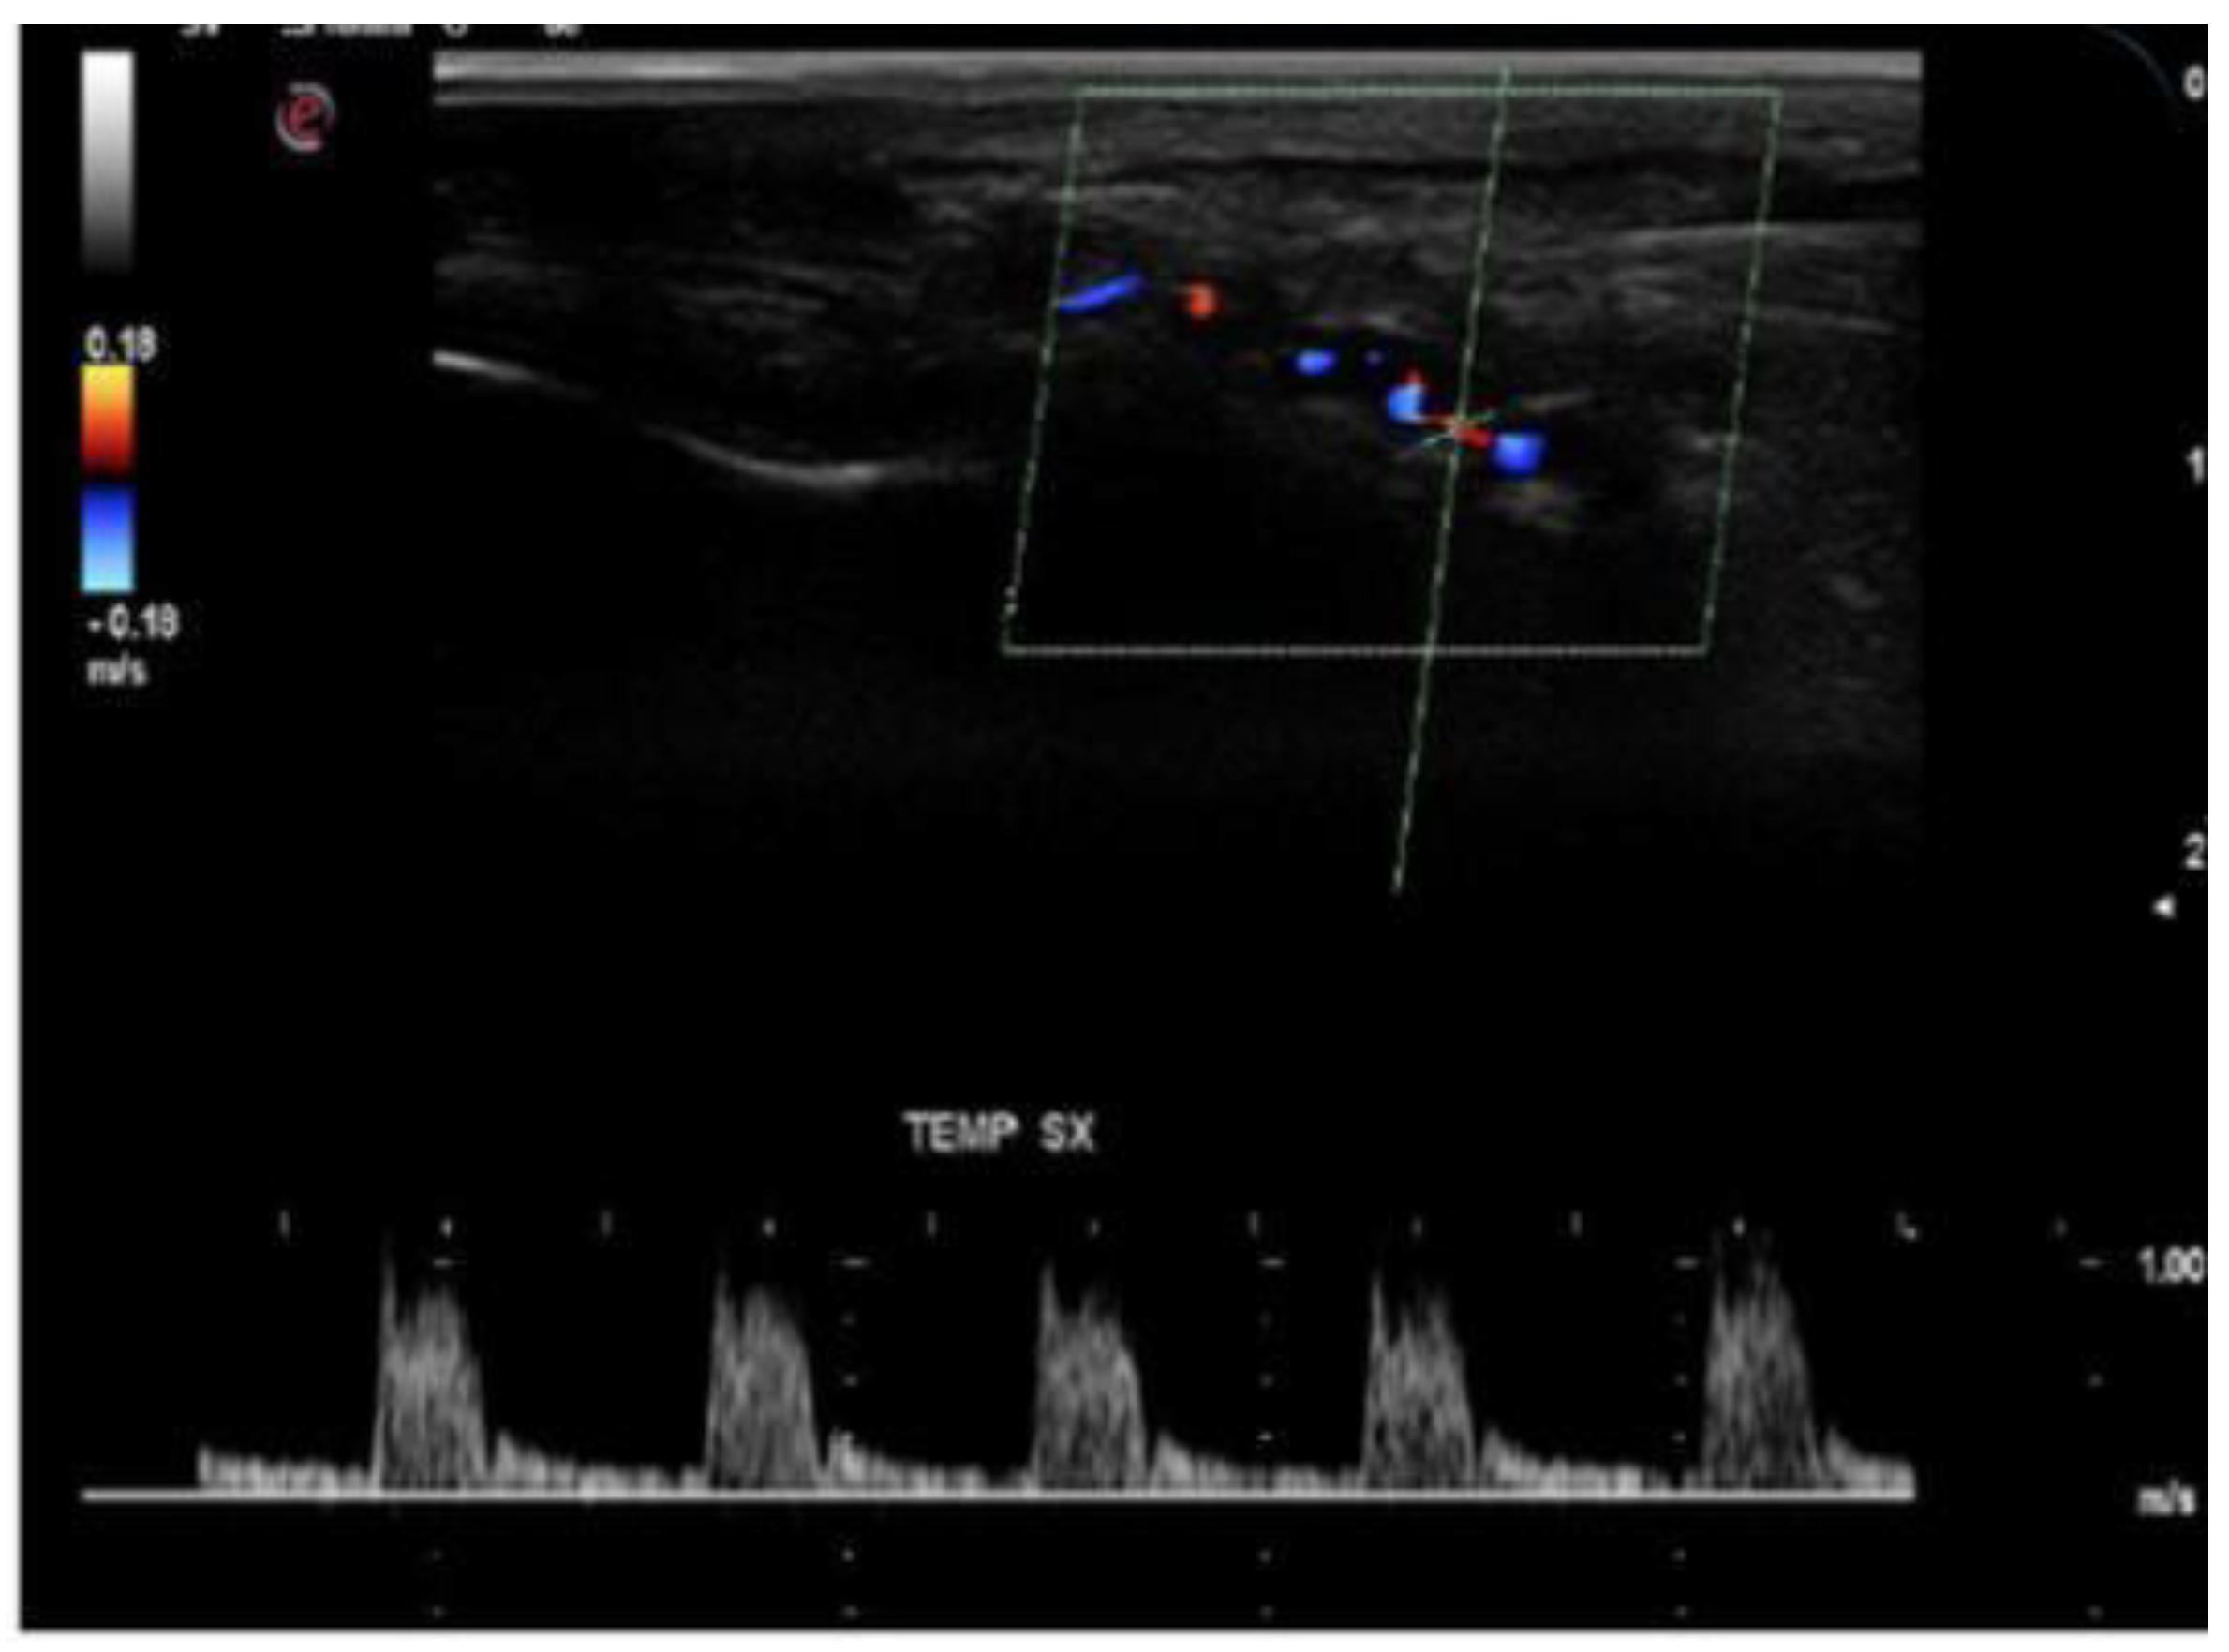

- Stenoses are characterized by aliasing and persistent diastolic flow by colour Doppler US. The peak systolic velocity (PSV) assessed within the stenosis area by pulsed-wave Doppler US is two or more times greater than the PSV recorded in the prestenotic segment of the vessel, with turbulence at the level of stenosis, associated with diminished velocities distal to the stenosis [30,31,32,33,34,35,36,37,38,39,40,41] (Figure 3) [11].

- c.